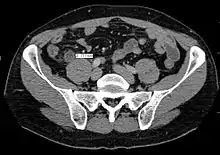

Coronal CT scan of a person initially suspected of having appendicitis because of right-sided pain. The CT shows in fact an enlarged inflamed gallbladder that reaches the right lower part of the abdomen.

Children: Gastroenteritis, mesenteric adenitis, Meckel's diverticulitis, intussusception, Henoch–Schönlein purpura, lobar pneumonia, urinary tract infection (abdominal pain in the absence of other symptoms can occur in children with UTI), new-onset Crohn's disease or ulcerative colitis, pancreatitis, and abdominal trauma from child abuse; distal intestinal obstruction syndrome in children with cystic fibrosis; typhlitis in children with leukemia.

Women: A pregnancy test is important for all women of childbearing age since an ectopic pregnancy can have signs and symptoms similar to those of appendicitis. Other obstetrical/gynecological causes of similar abdominal pain in women include pelvic inflammatory disease, ovarian torsion, menarche, dysmenorrhea, endometriosis, and Mittelschmerz (the passing of an egg in the ovaries approximately two weeks before menstruation).[63]

Men: testicular torsion

Adults: new-onset Crohn disease, ulcerative colitis, regional enteritis, cholecystitis, renal colic, perforated peptic ulcer, pancreatitis, rectus sheath hematoma and epiploic appendagitis.

Elderly: diverticulitis, intestinal obstruction, colonic carcinoma, mesenteric ischemia, leaking aortic aneurysm.